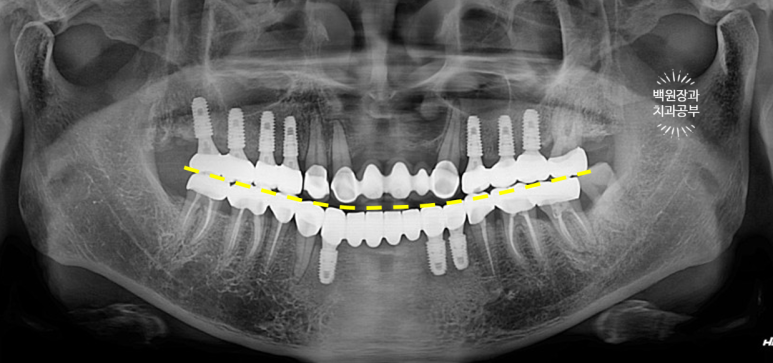

치과용 파노라마 엑스레이를 보시면 더 드라마틱한 변화를 느끼실 수 있어요.

다수의 치아가 씌워지고, 임플란트로 회복되어 마치 사이보그같은(?!) 느낌이 들긴 하지만,

정갈하게 치료가 잘 된 느낌입니다.!!!

임플란트의 위치가 적절히 배치되어 있어, 임플란트에서 크라운까지 이어지는 emergency profile이 예술이네요.

들쭉날쭉한 치아 없이 조화로운 교합이 형성되어 있는 것을 보실 수 있을거에요.

교합평면도 가지런하게 형성되어 보입니다.